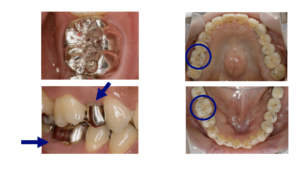

第一大臼歯には7~8点の接触点が必要といわれています。

- 咬む接触点が

保険外に比べ少ない ( 2 ~3点) - 適合精度に限界がある

- 咬む接触点の数が多く、

きちんと咬み合わせる事ができる - 適合精度 30~40ミクロン